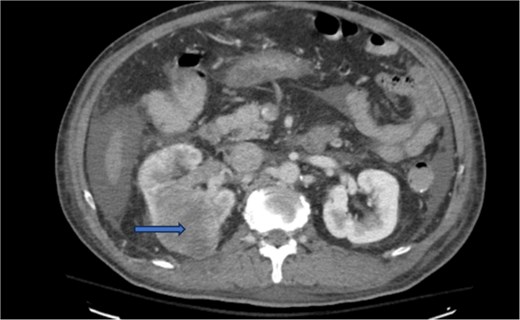

Diagnostic imaging began with a chest X-ray that indicated bilateral pleural effusions. An abdominal ultrasound detected a 4.6 × 4.2 × 4.3 cm echogenic lesion in the right hepatic lobe. Further imaging with a computed tomography (CT) scan of the chest, abdomen, and pelvis revealed a large mass originating from the posterior aspect of the right mid-kidney consistent with RCC (Fig. 1). The mass associated with thrombus extended into the renal sinus and collecting system, traveled along the right renal vein to the inferior vena cava (IVC), and projected into the right atrium (Figs 2 and 3). During hospitalization, bilateral lower extremity pain led to the diagnosis of bilateral deep vein thromboses via duplex venous ultrasound. Echocardiography showed normal left ventricular ejection fraction, impaired diastolic filling, mildly increased ventricular wall thickness, and an echogenic mass extending from the right atrium into the IVC consistent with the tumor thrombus.

CT chest abdomen and pelvis with contrast showing middle portion of right with tumor during venous phase venous phase.